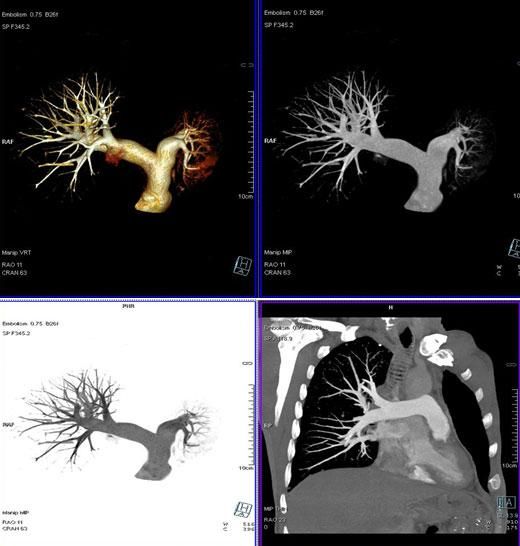

3、肺動脈血管成像:

該機掃描覆蓋範圍廣、時間短,多種後處理分析軟件能顯示各血管細小分支,可以清晰顯示動脈瘤、動脈夾層、血管畸形、血管狹窄及動脈粥樣硬化斑塊等,适用于頭頸部血管成像、肺動脈成像、胸腹部血管成像及四肢血管成像。